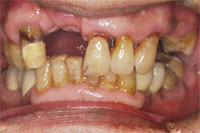

ある日突然前歯がグラグラしてきて折れてしまった患者様の症例

食事中に前歯がぐらぐらしてきて、最初のころは、しばらく放っておいたそうですが、しばらくすると、前歯がついに折れてしまったということです。

患者様が吉本歯科医院に来院された時には、その他の歯もグラグラになっている部分があることが診断でわかりました。患者さまの自覚症状としては、「とにかく前歯をくっつけて欲しい」ということでした。

吉本歯科医院においては、口内写真とパノラマレントゲンを撮影し、まずは顎の骨の状態まで詳しく確認しました。

噛み合わせが非常に悪く、上の歯が下の歯にすっぽりと覆いかぶさっておりまともに噛めていない状態であることがわかりました。.

院長の吉本が診断したところ次のような診断結果となりました。

・もともとの咬合不全(咬み合わせの悪さ)による前歯の破折

・歯を支える骨も溶けて薄くなってしまっている状態